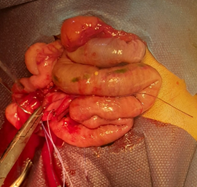

Abdominal X-ray showed absence of gas on the right side of the abdomen and the pelvis as shown in Figure 1.

Figure 1 Plain abdominal xray showing absence of gas on the right side of the abdomen and the pelvis.